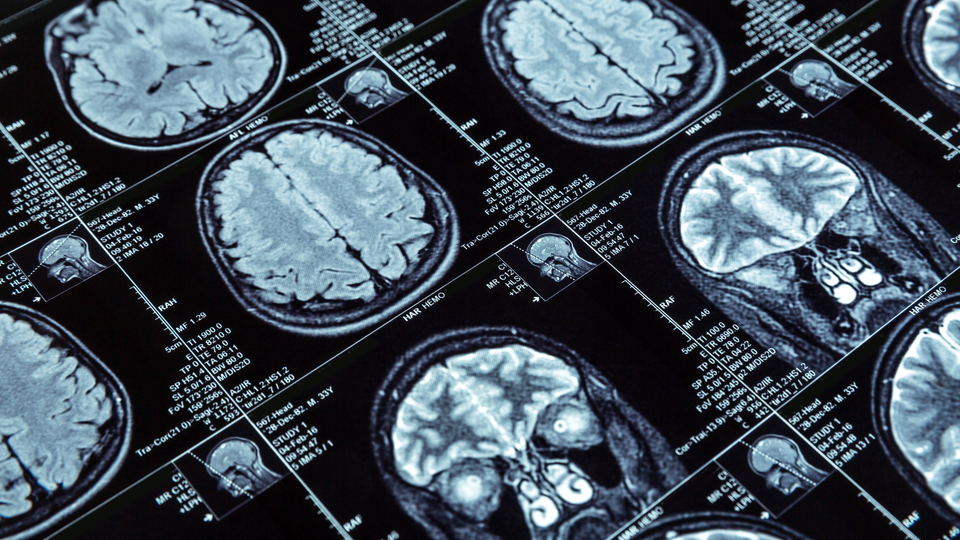

Prof. Dr. Bebek, Covid sonrası dönemde, hastalarda epilepsi nöbet sıklığındaki değişikliklerde Covid geçmişi olup olmadığının sorgulandığını belirterek "Bildiğimiz ve takip ettiğimiz hastada nöbet tekrarı olduğunda bu sorgulamayı yapıyoruz. Uykusuz mu kaldın, ilacını mı aksattın, Covid mi geçirdin gibi. Çoğu insan hastalığı geçirdim diyor tabii ki. Ama Covid sırasında epilepsi nöbetinin tekrarladığını söyleyen hasta sayımız o kadar yüksek değil. Daha önce epilepsi hastalığı ile gelmeyen Covid sonrası nöbet ile karşımıza gelen vakalarda da bu sorgulamaları yapıyoruz. Covid'in beyni etkilediği ya da vücudu ağır etkilediği durumlarda yeni epilepsi nöbetlerinin ortaya çıkma riski artıyor. Beyni bu kadar ağır etkilenmiş olan bireyde epilepsi nöbetinin yanı sıra diğer nörolojik bulgular da eşlik edebiliyor. Örneğin ağır durumdaki Covid hastalarının yaklaşık yüzde 30'unda nörolojik tutulumun da olduğu biliniyor. Bunların içerisinde inme de var, nöbet de var. Bunlar bir arada seyredebilen durumlardır çoğu zaman" dedi.